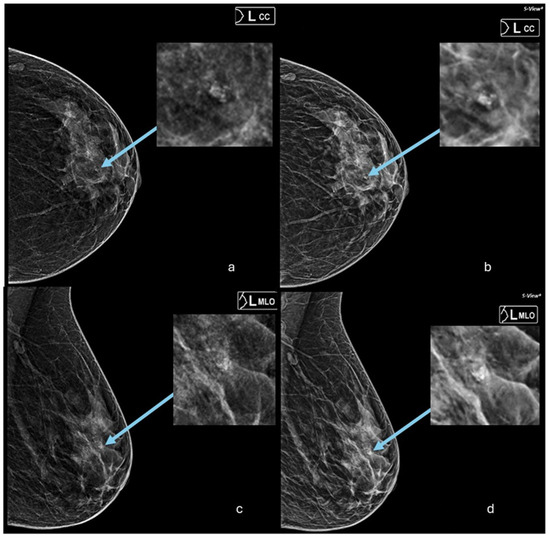

3.1. Accuracy of SM Compared to DM in Breast Cancer Detection and Diagnosis

3.2. Agreement Between Mammography and Synthetic Mammography in Cancer Visibility, Breast Density, Cancer Size, and Microcalcification Detection